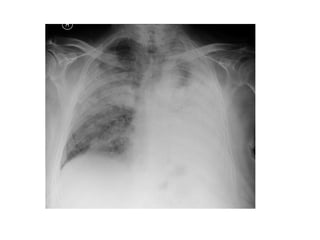

1-Diffuse pulmonary hemorrhage

Localized Diffuse